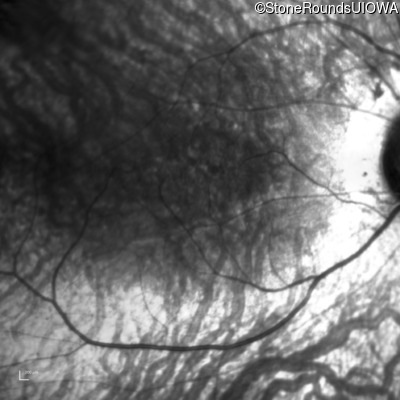

Infrared Fundus Photograph - Right - 20/40

Exemplar